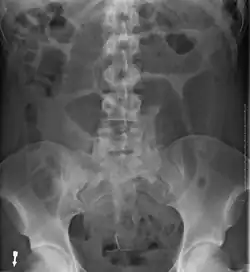

After taking a thorough history, the diagnosis of colonic volvulus is usually easily included in the differential diagnosis. Abdominal plain x-rays are commonly confirmatory for a volvulus, especially if a coffee bean sign is seen. These refer to the shape of the air-filled closed loop of the colon, which forms the volvulus. Should the diagnosis be in doubt, a barium enema may demonstrate a "bird's beak" at the point where the segment of proximal bowel and distal bowel rotate to form the volvulus.

This area shows an acute and sharp tapering and looks like a bird's beak. If a perforation is suspected, barium should not be used due to its potentially lethal effects when distributed throughout the free intraperitoneal cavity. Gastrografin, which is safer, can be substituted for barium.